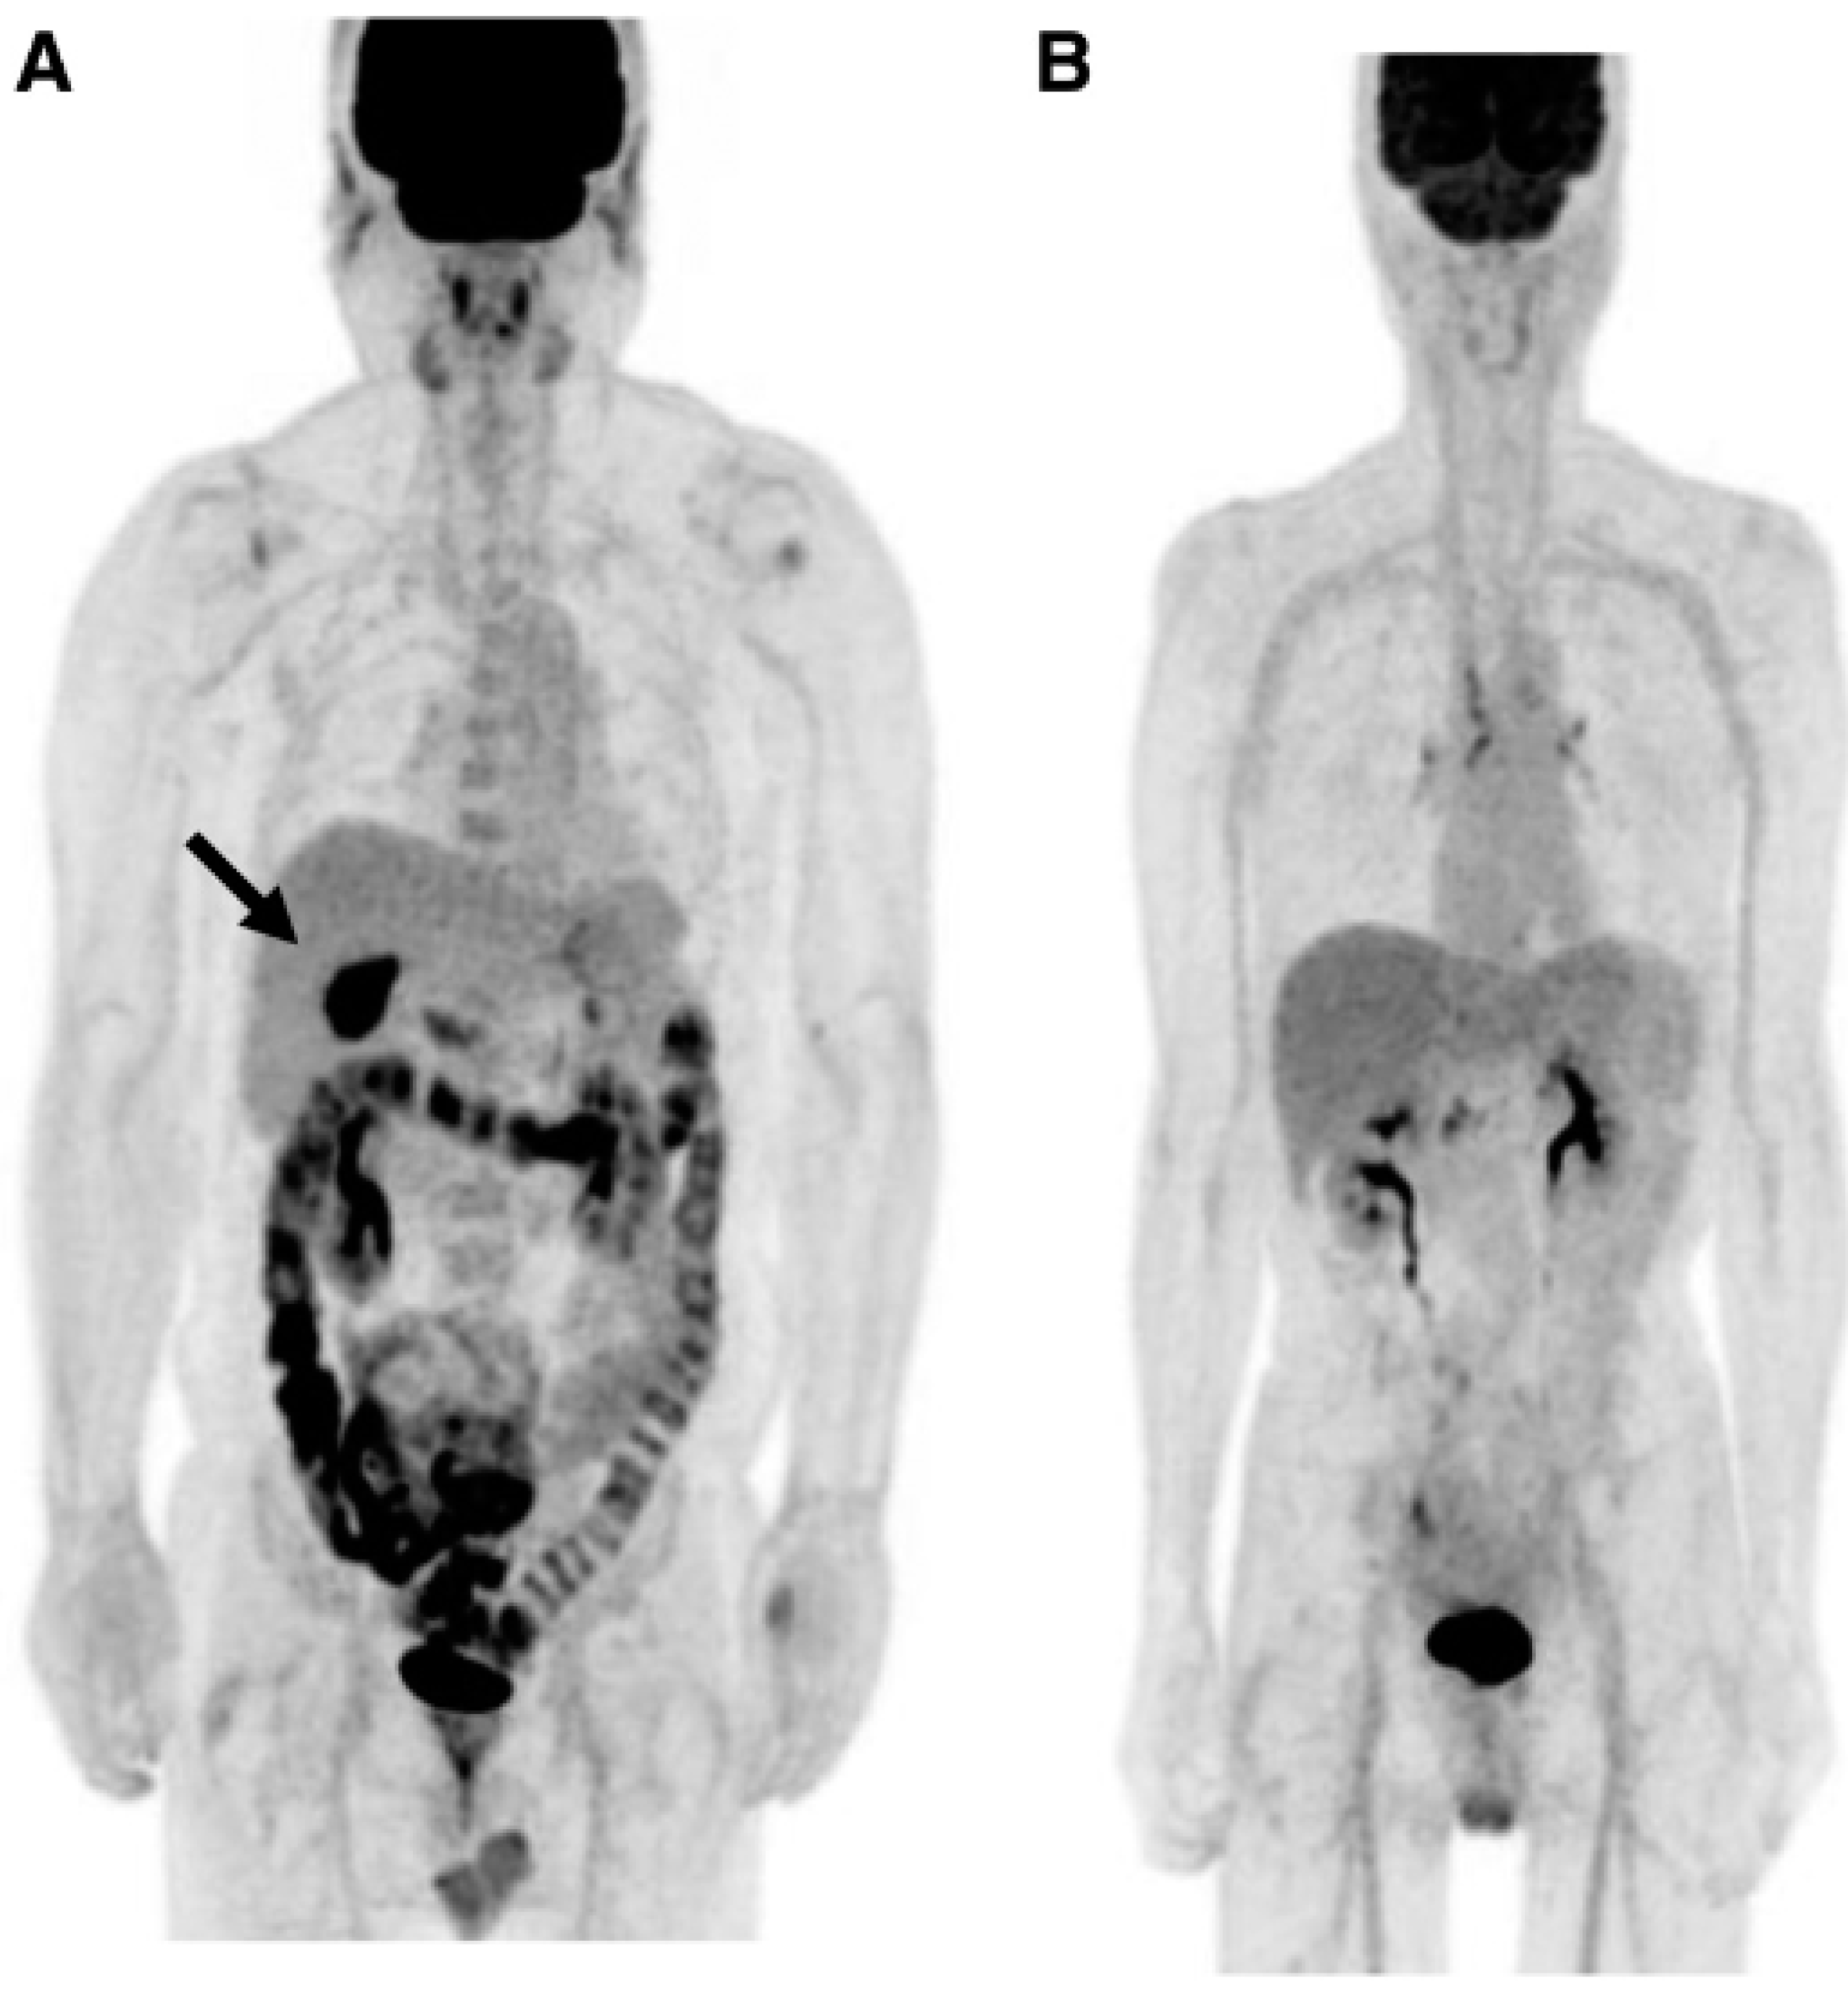

Accumulation of F18-FDG in the large intestine (Figure 4) has been found also in persons who regularly use laxatives (136-137).SUVmax can even reach levels,which simulate those of colorectal neoplasms (Figure 5) in patients with chronic constipation (138).

Figure 4. PET-pictures of early scans (upper row) and of late FDG-scans(lower raw) after oral administration of laxatives. The arrows in the upper row of PET-scans shows the different patterns of accumulation of the tracers in the large intestine.From Chen Y-K et al.(137, with permission).

Figure 5. Accumulation of F18-FDG(after intravenous administration) in the coecum and ascending colon (upper panel,long arrow) of a patient suffering from a mild diabetes (HbA1c=6.8%) and from chronic constipation treated with anthraquinone laxatives as demonstrated by the presence of melanosis coli at colonoscopy performed to exclude colon cancer (lower panel,short arrow).From Katsumata R (138).